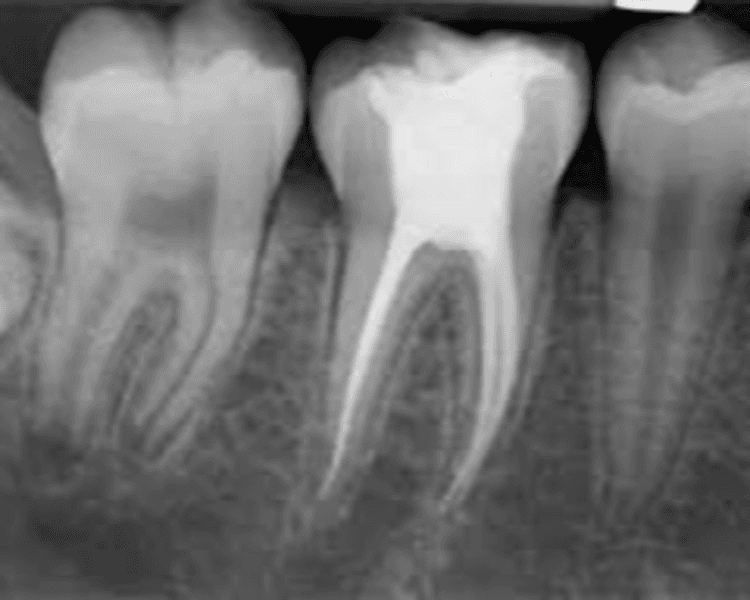

La endodoncia es un procedimiento odontológico que actúa sobre la pulpa dental, se utiliza para tratar caries profundas que han atravesado el esmalte y la dentina y han llegado a la pulpa, produciendo una infección de la misma conocida como pulpitis. La técnica consiste en acceder a esta zona profunda de la pieza dental, extraer la pulpa mediante instrumentos especiales, y rellenar la cavidad con un material inerte.